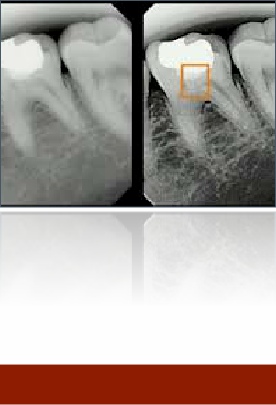

X-rays

A diagnostic tool that allows us to see under fillings and in between teeth.  They are vital for treatment planning.

Digital x-rays can be enhanced to provide more clearer information.